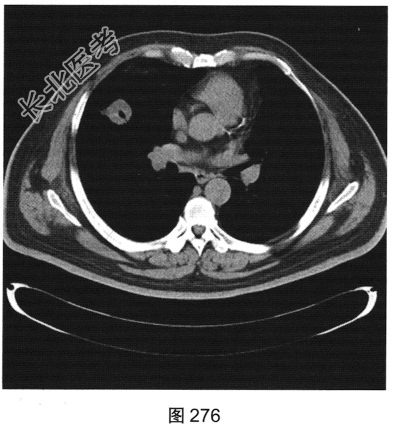

- [材料题] 患者男性,56岁,因“查体发现右肺中叶结节半个月余”就诊。患者于半个月前在小汤山疗养院查体时行胸部X线检查,显示右肺中叶结节,遂至我院就诊。行胸部CT检查:显示右肺中叶外侧段有一肿块影,大小为3.6cm×3.2cm,可见分叶,边缘有毛刺,内见空泡影,CT值约15HU,增强后CT值约25HU。患者近期无咳嗽、咳痰,无咯血、胸痛,无发热、乏力,无声音嘶哑、饮水呛咳,无头痛、头晕,未予特殊治疗。为进一步诊治,以“右肺占位”收入我院。患者精神状态良好,体力、食欲、睡眠正常,体重无明显变化,大、小便正常。胸部CT检查如图274~图277所示。

- 多项选择题2.根据患者临床病史和影像特征,您的诊断是( )

A、周围型肺癌

B、真菌球

C、结核球

D、寄生虫

E、良性肿瘤

F、机化性肺炎